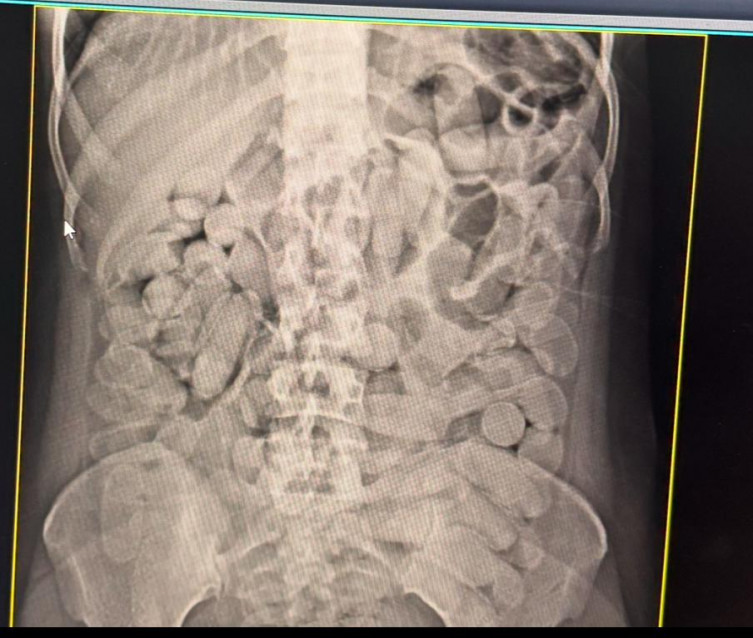

Momento em que cápsulas de droga são descobertas em garrafas de energético